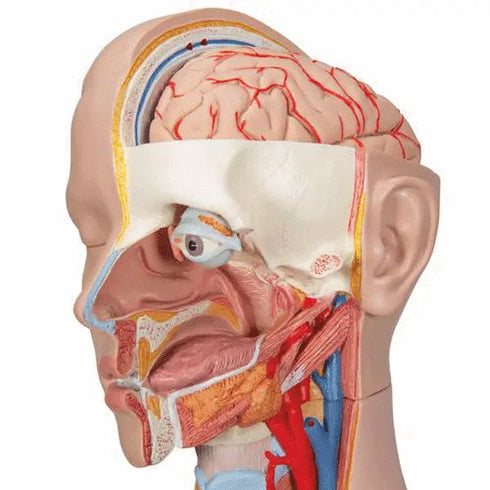

- cap (3 parti);